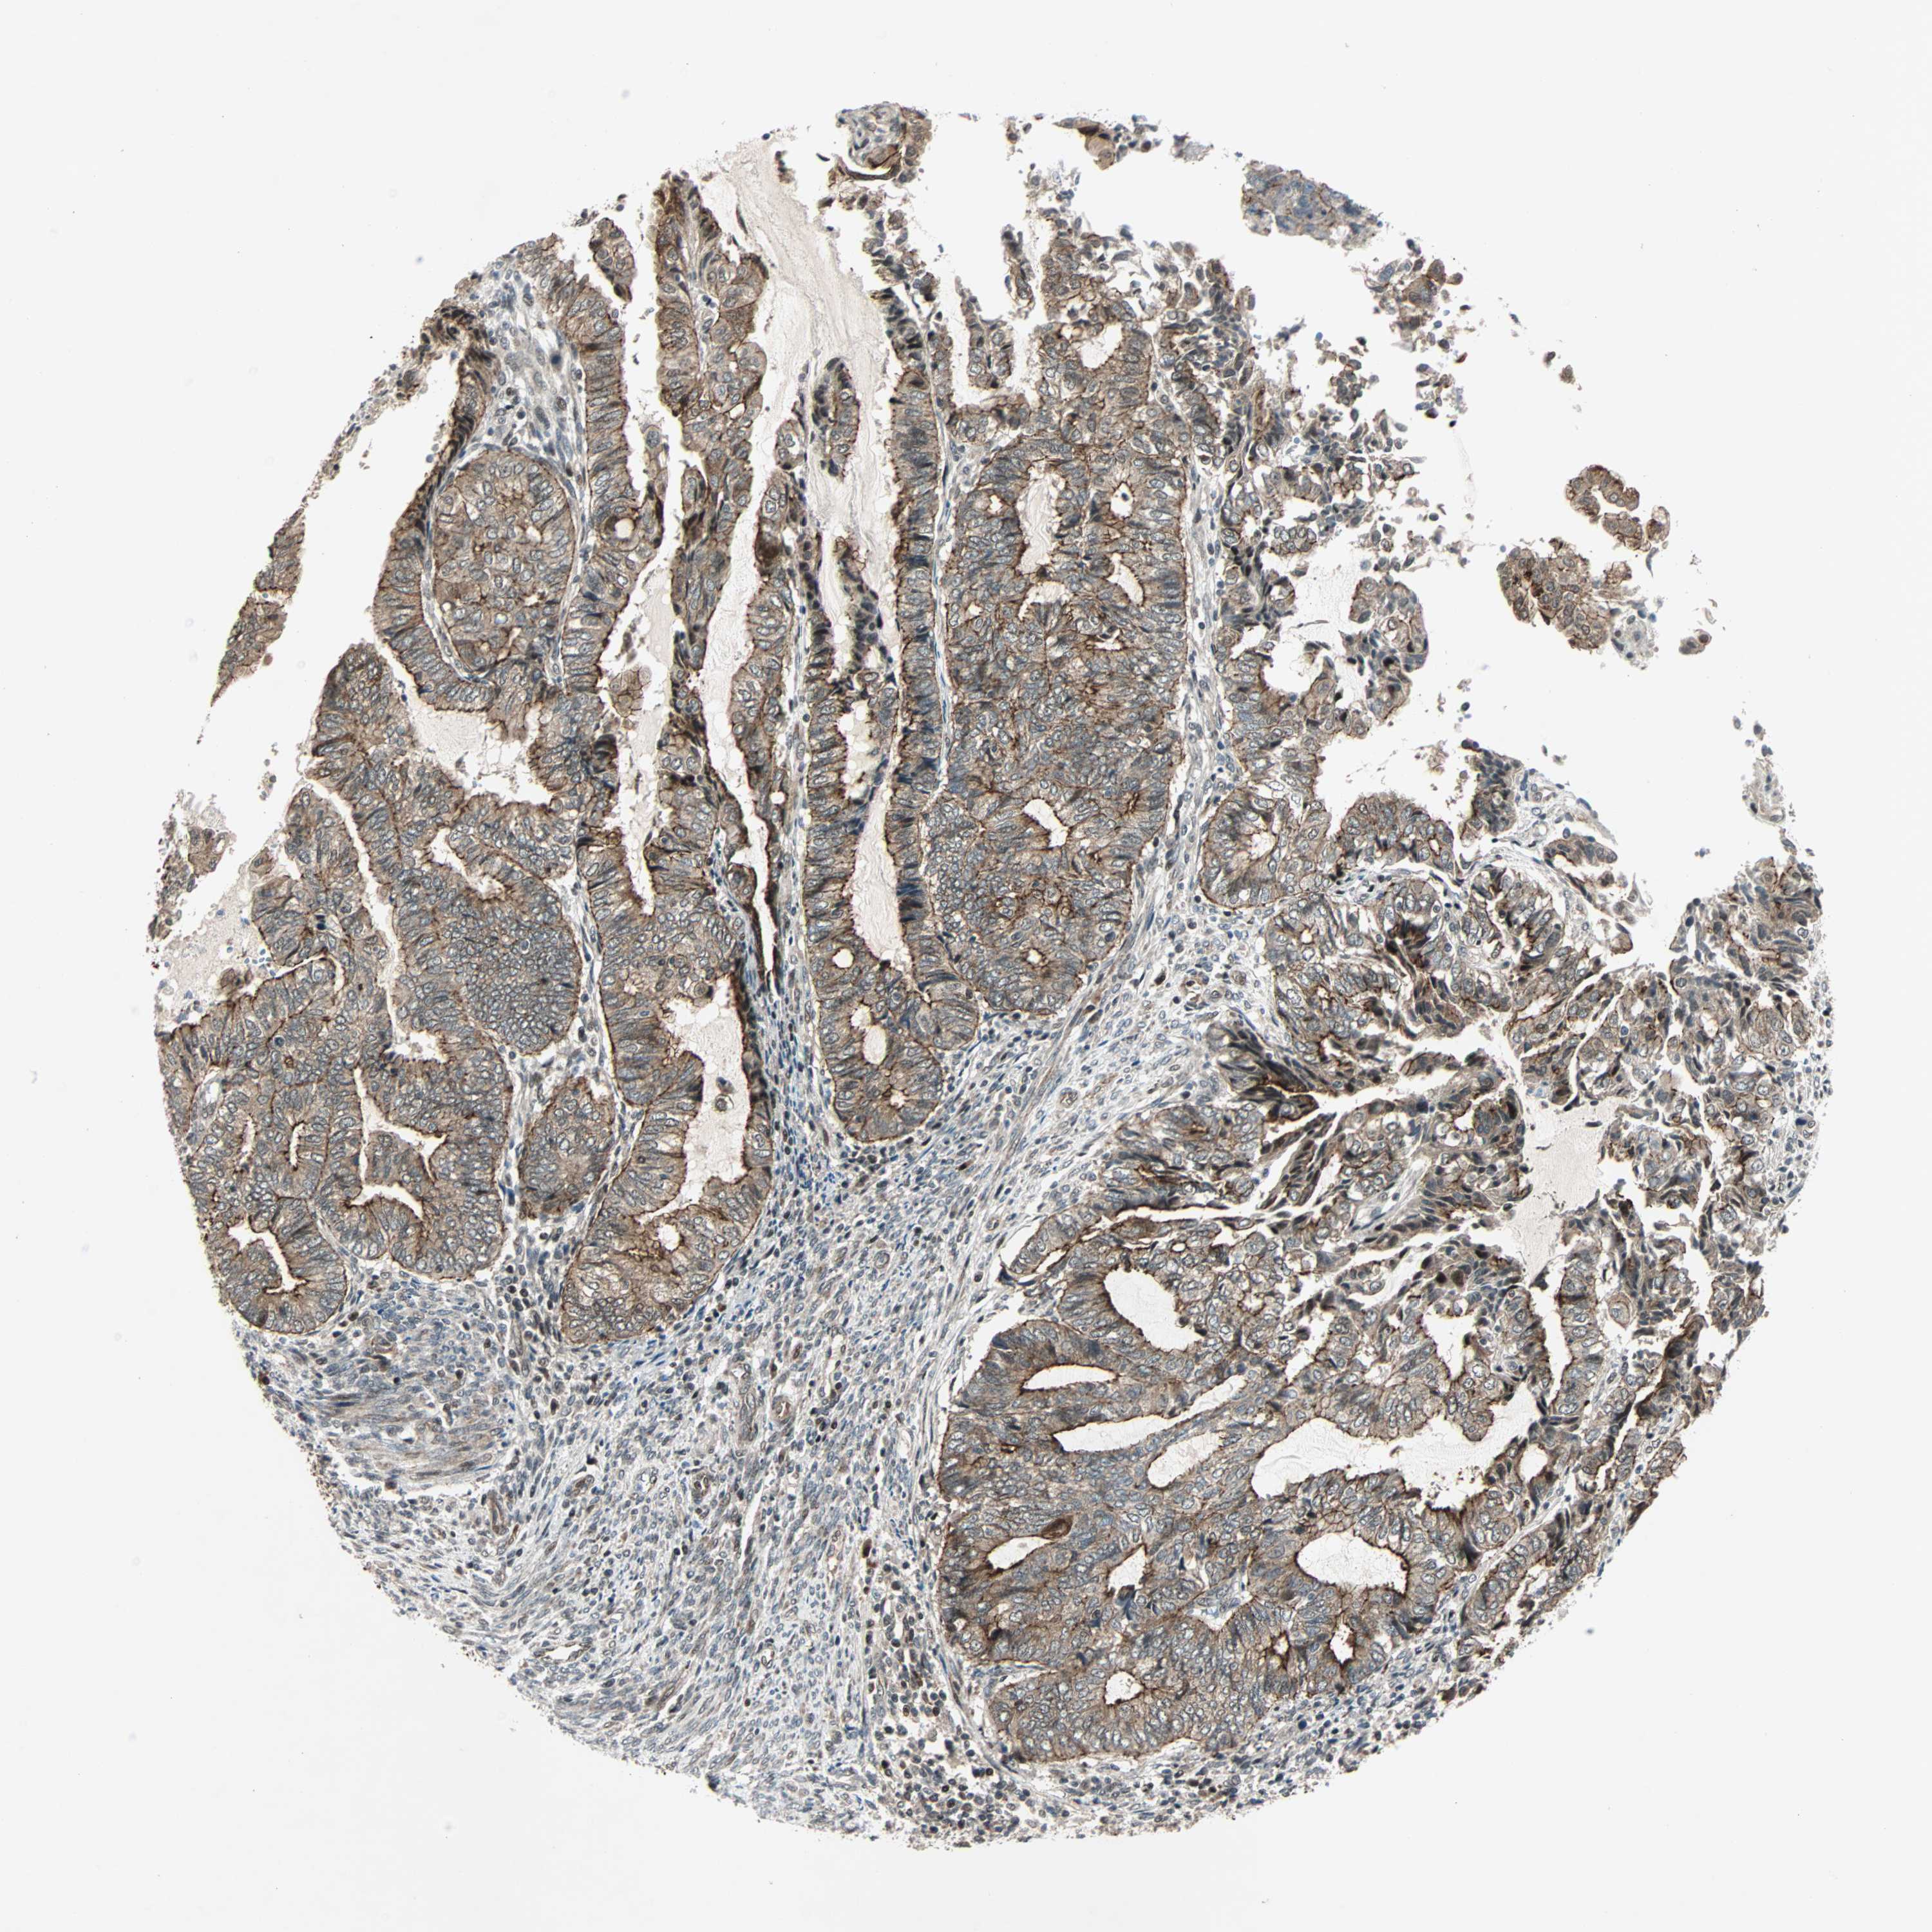

ENDOMETRIAL CANCER - Protein expressioni

A mouse-over function shows sample information and annotation data. Click on an image to view it in a full screen mode. Samples can be filtered based on level of antibody staining by selecting one or several of the following categories: high, medium, low and not detected. The assay and annotation is described here.

Note that samples used for immunohistochemistry by the Human Protein Atlas do not correspond to samples in the TCGA dataset.

Antibody stainingi

Antibody staining in the annotated cell types in the current human tissue is reported as not detected, low, medium, or high, based on conventional immunohistochemistry profiling in selected tissues. This score is based on the combination of the staining intensity and fraction of stained cells.

Each image is clickable and will lead to virtual microscopy that enables deeper exploration of all samples and also displays staining intensity scores, fraction scores and subcellular localization as well as patient and tissue information for each sample.

Antibody HPA008228

Staining

High

Medium

Low

Not detected

Intensity

Strong

Moderate

Weak

Negative

Quantity

>75%

75%-25%

<25%

None

Location

Nuclear

Cytoplasmic/membranous

Cytoplasmic/membranous,nuclear

Adenocarcinoma, NOS